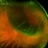

- macula off retinal detachment, left eye, OPTOS CALIFORNIA, ultra-widefield image, scanning laser ophthalmoscope

- An ultra-widefield fundus image of a 65 year old male with a Macula Off Retinal Detachment. Patient's vision at the time of the image was CF at 6 Feet and surgical options were discussed. Fluid-gas exchange was performed without complications.